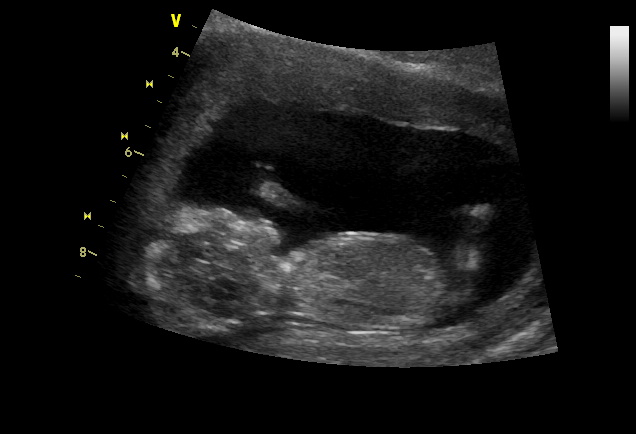

Už jsme byli s manželem na screeningu a bylo to nezapomenutelné. Poprvé jsme slyšeli srdíčko mimča a za neuvěřitelných 11 dní od poslední návštěvy náš malý vyrost o 3 cm. V pátej jsme byli v 12+5 a měřili 6.33cm. Vyšetření dopadlo výborně, jsme zdraví a posílám malý obrázek. Připadá mi jako ve vaně